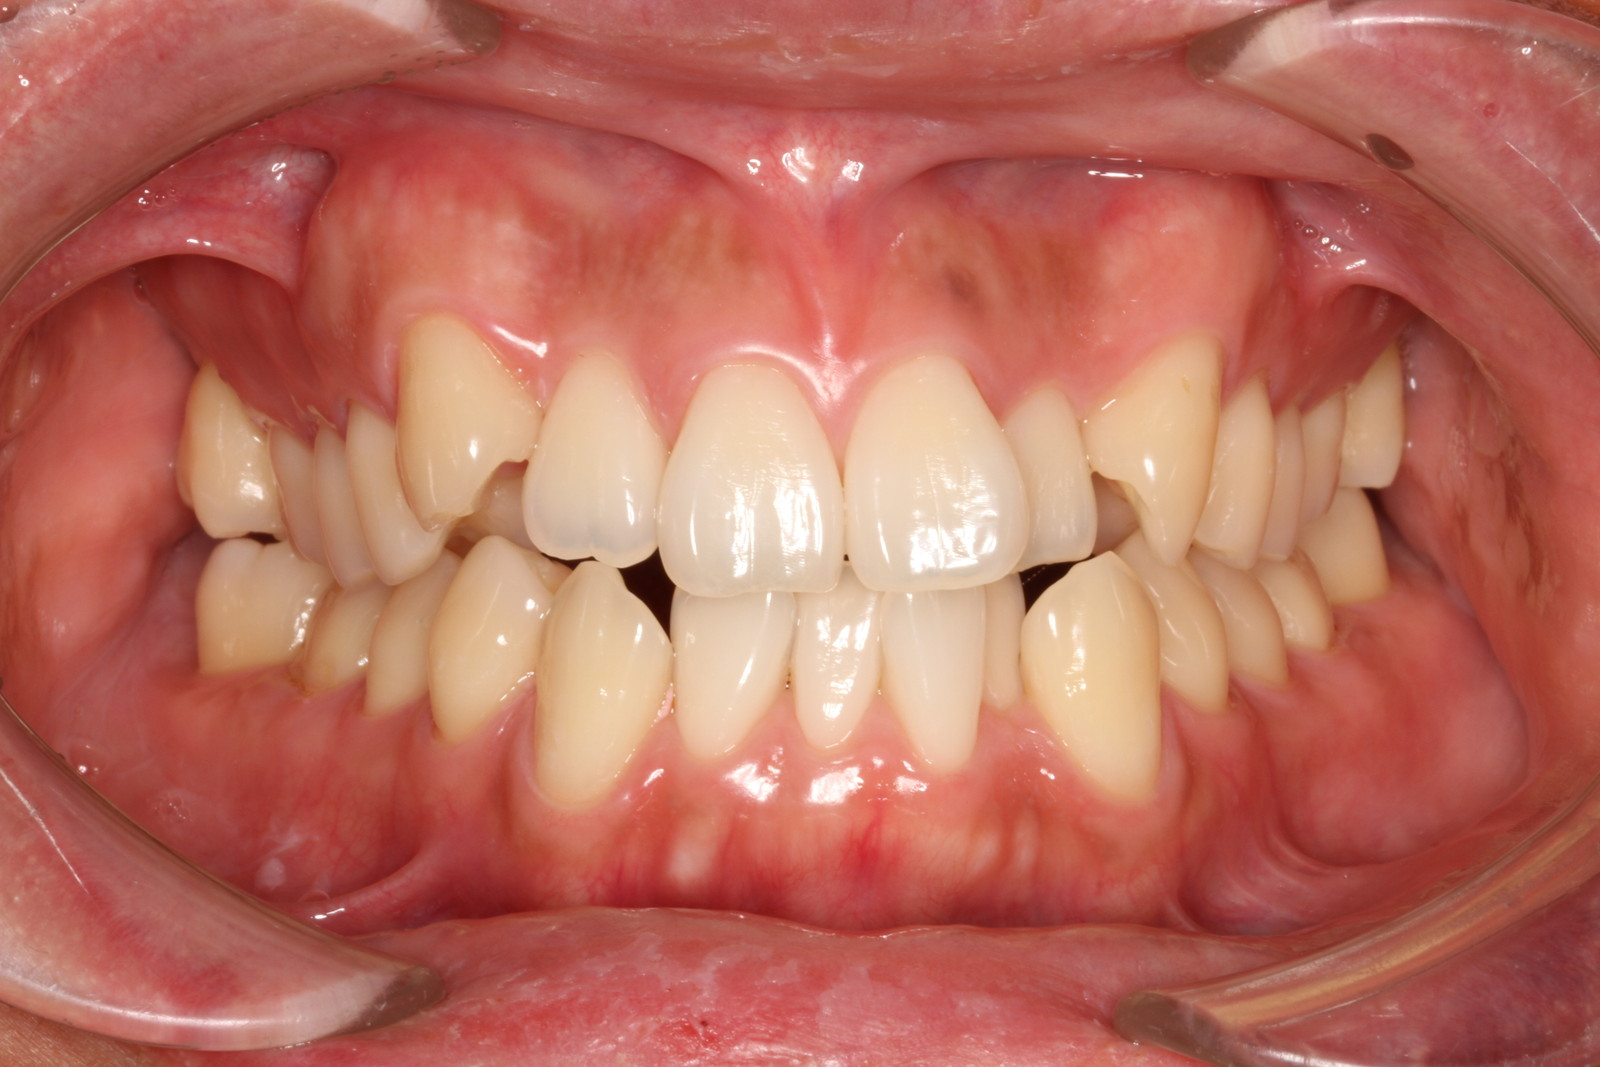

問診を行い、お口の悩みや希望を確認します。レントゲン撮影や口腔内写真の撮影など、必要に応じた精密検査を行います。